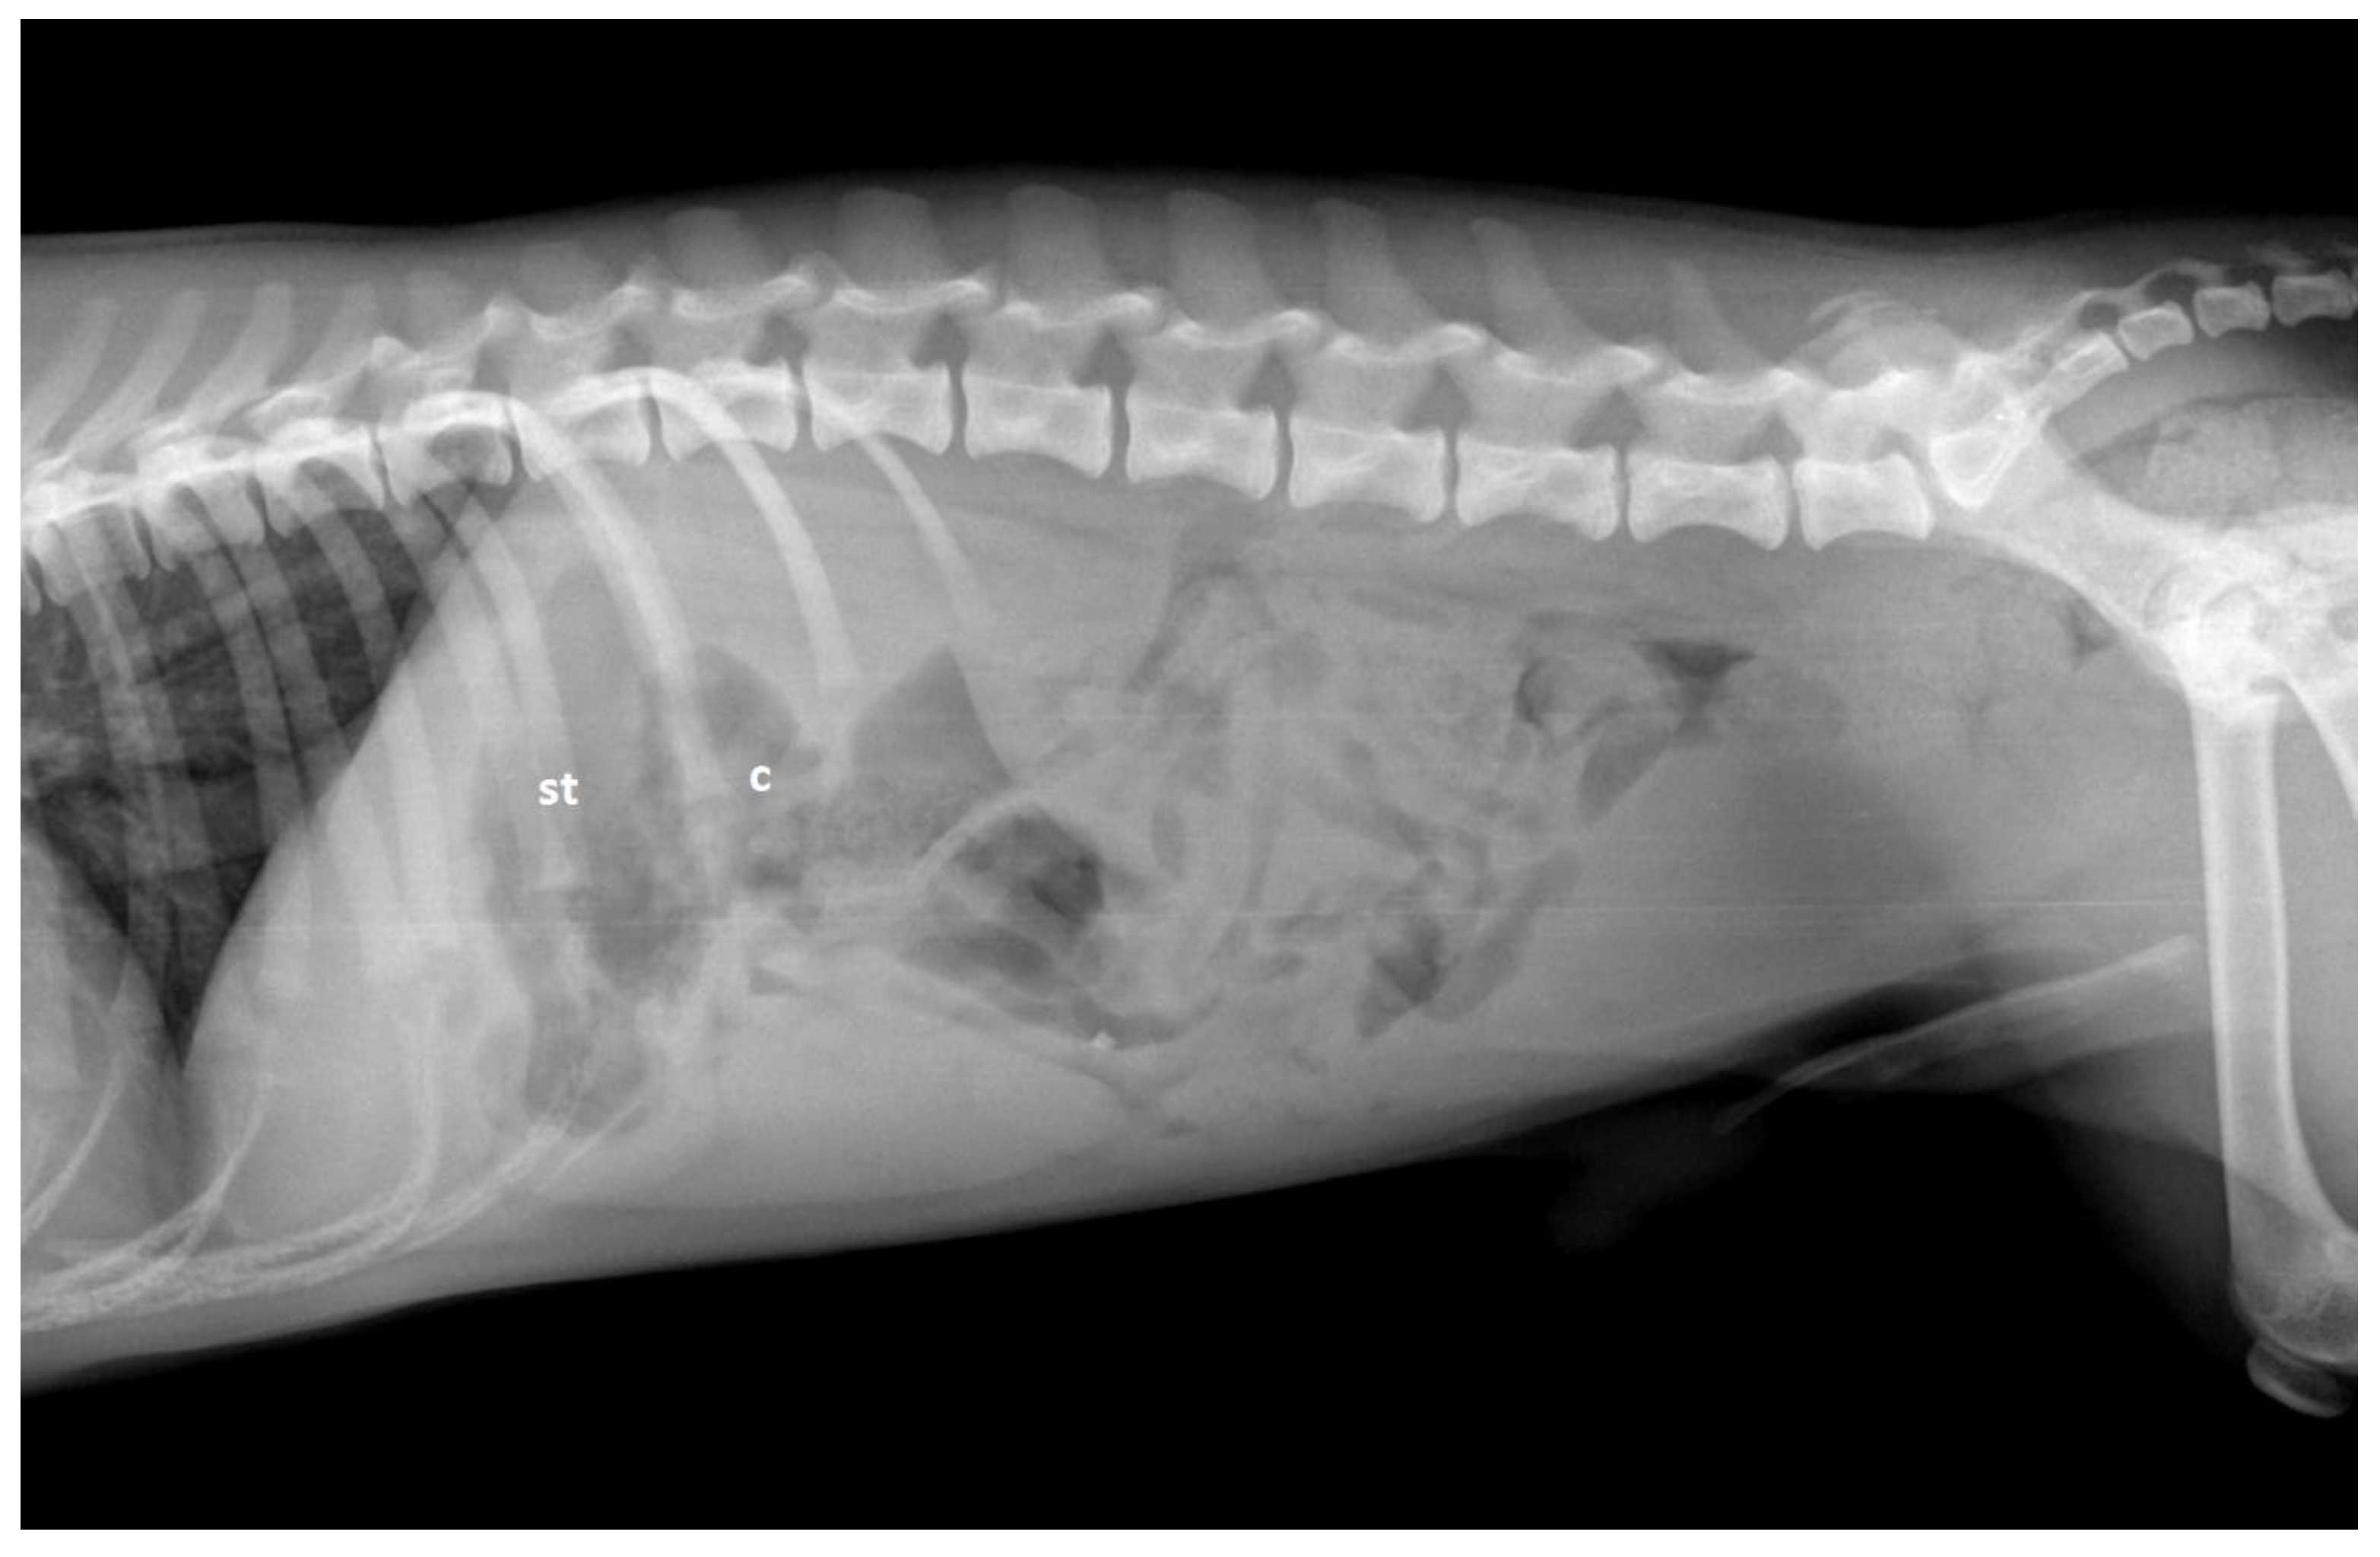

9. Diagnostic Imaging